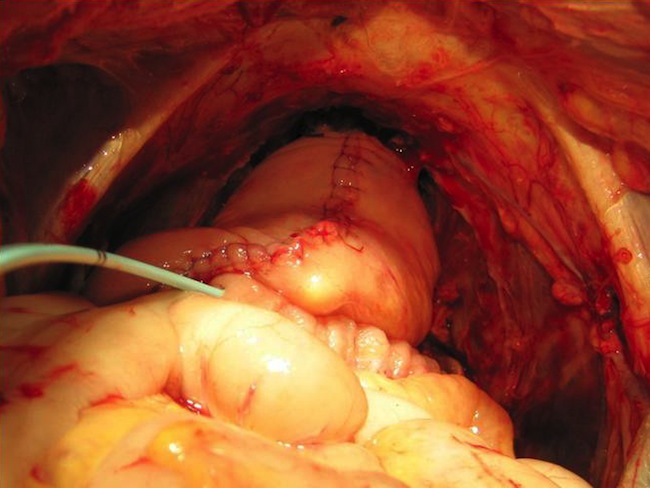

Хирургическое вмешательство во всех случаях предполагало после лапаротомии выполнение ревизии брюшной полости с уточнением местной распространенности опухоли и дополнительной оценки признаков отдаленного метастазирования. Далее мобилизовали слепую кишку, восходящий, сигмовидный и ректосигмоидный отделы ободочной кишки. Париетальную брюшину рассекали от нижнегоризонтальной ветви двенадцатиперстной кишки вдоль аортокавального промежутка, общих и наружных подвздошных сосудов.

Производили диссекцию парааортальной, межаортокавальной и паракавальной клетчатки и лимфатических коллекторов и далее по ходу общих, наружных и внутренних подвздошных сосудов, а также из запирательный ямок от перефирии к удаляемому препарату.

Затем выделяли, лигировали и пересекали нижнюю брыжеечную артерию в месте ее отхождения от аорты. Лигировали и пересекали сосуды брыжейки сигмовидной кишки и пересекали саму кишку, отступив от места ее вовлечения в опухолевый конгломерат не менее 10 см. Далее острым путем производили выделение задней и боковых стенок прямой кишки до верхушки копчика.

У мужчин выделяли, лигировали и пересекали семявыносящие протоки с обеих сторон у внутреннего кольца пахового канала. У женщин лигировали и пересекали круглые и воронкотазовые связки матки. При выполнении полных эвисцераций малого таза мобилизовали и пересекали мочеточники с обеих сторон на уровне их пересечения подвздошных сосудов. Последние интубировали мочеточниковыми катетерами типа «pig tail» №9 Schr до почечных лоханок. Далее выполняли мобилизацию мочевого пузыря со стороны верхушки, боковых и задней поверхностей со всей паравезикальной клетчаткой. Поэтапно лигировали и пересекали верхние и нижние мочепузырные артерии. У мужчин пересекали пубопростатические связки, лигировали вены Санториниевого сплетения. Уретру пересекали на уровне проксимальной границы мембранозного отдела.

При выполнении инфралеваторных эвисцераций малого таза, на промежностном этапе вмешательства выполняли окаймляющий разрез кожи промежности от верхушки копчика до корня полового члена у мужчин и до наружного отверстия уретры – у женщин. Пересекали анокопчиковую связку и мышцу, поднимающую задний проход. Препарат удаляли со стороны брюшной полости единым блоком.

При сохранении тазового дна и выполнении континентной деривации мочи с формированием ортотопически дислоцируемого мочевого резервуара в уретру ретроградно вводили металлический буж №24 Schr и на проксимальный конец резецированной уретры накладывали 6 провизорных лигатур атравматическим монофиламентым шовным материалом (3/0) на 1, 3, 5, 7, 9, 11 часах условного циферблата. При планировании инконтинентной деривации мочи, или дистопичекой локализации мочевого резервуара уретру и влагалище герметично ушивали. Отступив от илеоцекального угла 15-20 см, выделяли сегмент подвздошной кишки длиной 40-45 см (для формирования J-необладера по модифицированной технологии Штудера) и 10-12 см (для формирования уростомы по Брикеру) с адекватным кровоснабжением. По границам выбранного участка подвздошную кишку пересекали. Непрерывность тонкой кишки восстанавливали формированием анастомоза по типу «конец в конец» однорядным швом (Викрил 4/0). Дефект брыжейки ушивали отдельными узловыми швами. Мобилизованный сегмент подвздошной кишки с питающей её брыжейкой низводили в полость малого таза. ¾ кишки детубулизировали по противобрыжеечному краю и формировали J-мочевой резервуар. Мочеточнико-резервуарные анастомозы формировали по методу Wallace единой площадкой в торец недетуболизированного сегмента подвздошной кишки, образующей мочевой резервуар. Анастомоз необладдера с проксимальным отделом уретры формировали на 3-х ходовом катетере Фоллея №20 Schr.

При деривации мочи по Брикеру с проксимальным сегментом подвздошной кишки анастмозировали мочеточники по методу Wallace. Дистальный конец кишечного сегмента выводили на переднюю брюшную стенку в правой подвздошной области – формировали уростому.

Восстановление толстокишечного сегмента пищеварительного тракта достигали формованием колоректального анастомоза «конец в конец». С этой целью всегда использовали циркулярный сшивающий аппарат. При невозможности анастомозирования проксимального и дистального участков толстой кишки, а также при задних и тотальных инфралеваторных эвисцерациях малого таза в левой подвздошной области формировали концевую колостому.

Операцию завершали восстановлением париетальной брюшины с размещением зоны уретероилеоанастомозов эктраперитонеально и дренированием брюшной полости через промежность двумя дренажами. Правый размещали в зоне уретероилеоанастомозов, левый – в малом тазу.